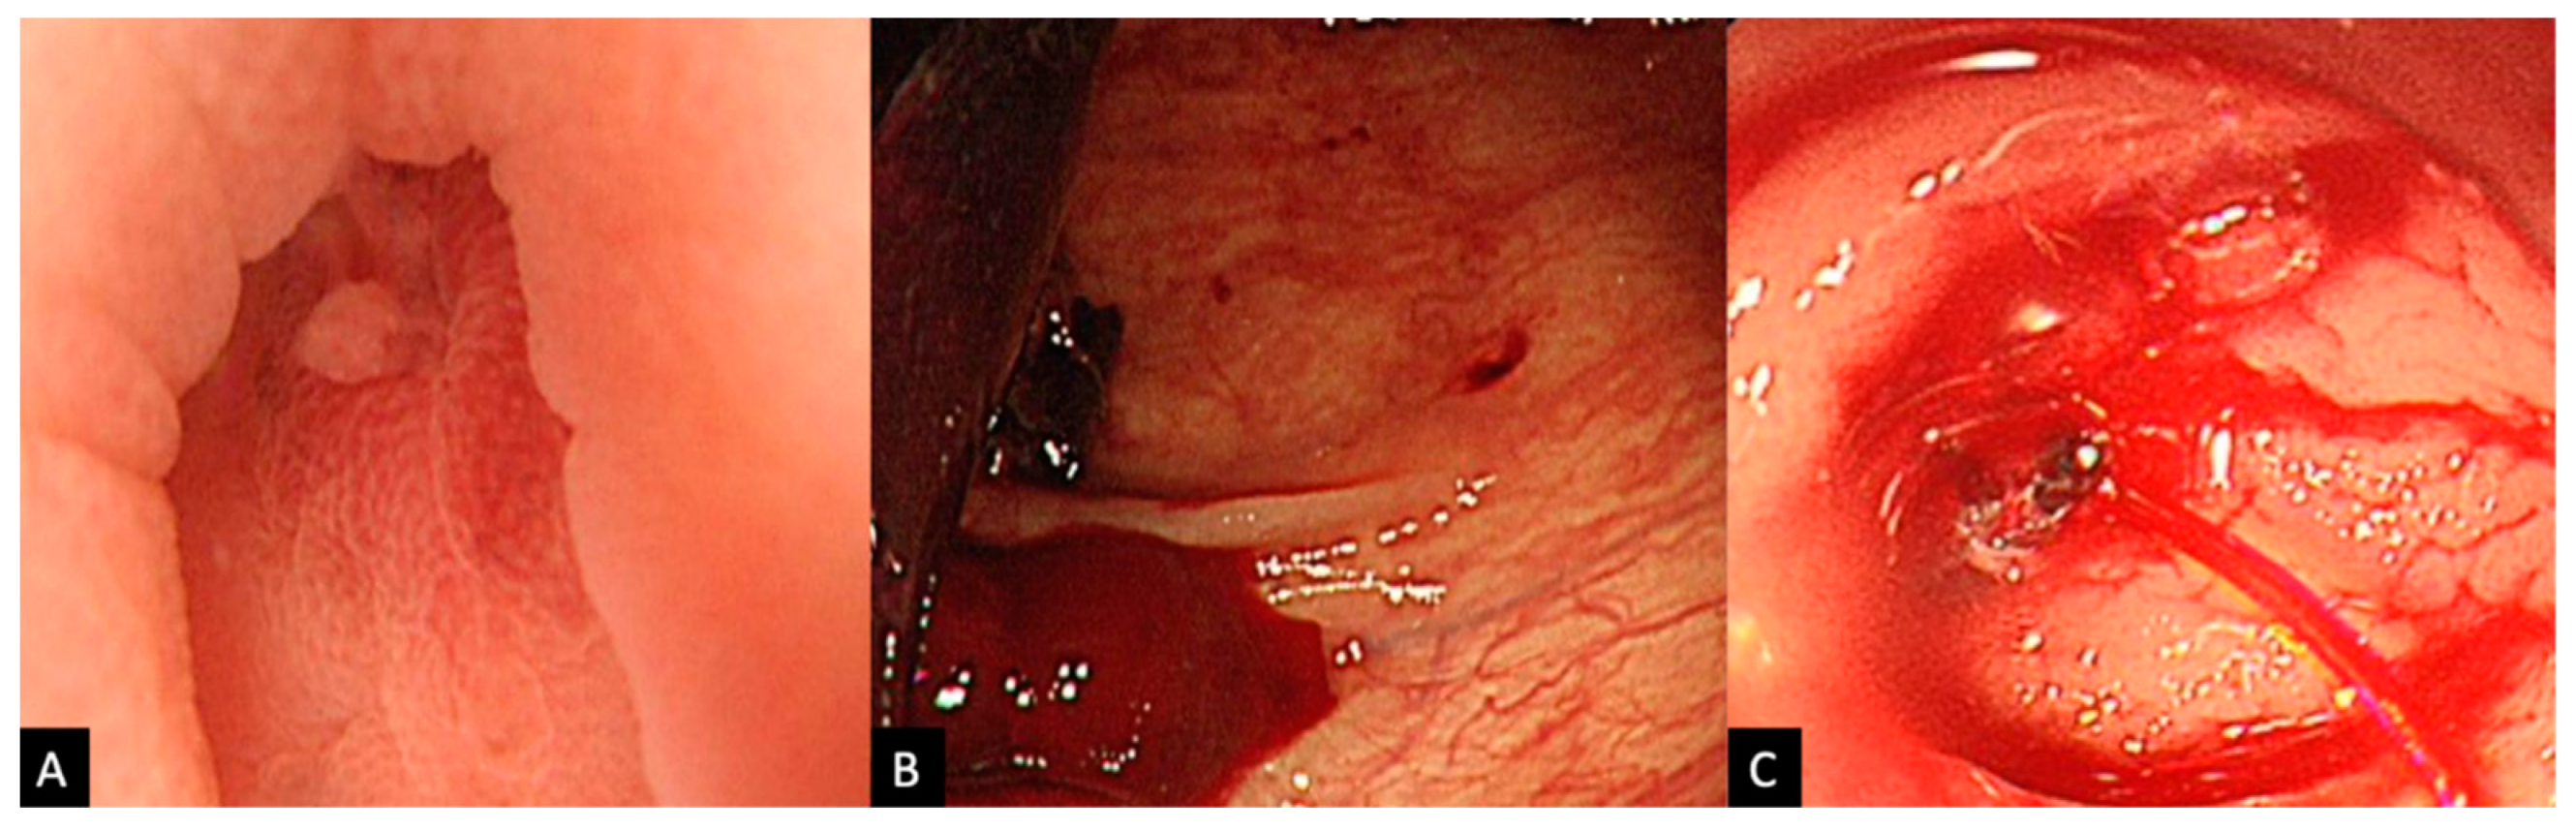

2.2. Procedure